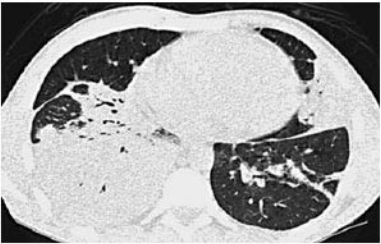

La TC de alta resolución de tórax (Figura 2) reveló opacificación extensa del espacio aéreo que afectaba el lóbulo inferior derecho con otras áreas de opacificación confluentes en lóbulo medio derecho, língula y lóbulo inferior izquierdo. Había también pequeñas bronquiectasias. No había linfadenopatías. El examen broncoscópico mostró vías aéreas normales; el lavado broncoalveolar (BAL) fue negativo para bacilos ácido-alcohol resistentes y también fue negativo para Pneumocystis jirovecii por PCR. Una biopsia transbronquial mostró infiltrados inespecíficos de células plasmáticas y linfocitos.

Figura 2. TC de tórax de alta resolución.

Una TC muestra extensa opacificación del espacio aéreo que afecta el lóbulo inferior derecho acompañado de áreas confluentes de opacificación en la língula y lóbulo inferior izquierdo y pequeñas bronquiectasias. Un área de opacicificación en el lóbulo medio derecho (no mostrado) estaba presente.

Aunque las densas áreas de condensación en ambos pulmones, como se ven en la TC son compatibles con el diagnóstico de neumonía bacteriana, también son compatibles tanto con blastomicosis como con BOOP. En particular por la naturaleza periférica de alguna de las áreas de consolidación que pueden ser indicativas de BOOP. La presencia de infiltrados de células plasmáticas y linfocitos en ausencia de neutrófilos argumenta contra el diagnóstico de neumonía bacteriana, y la ausencia de eosinófilos es un dato importante en contra de neumonía eosinofílica.